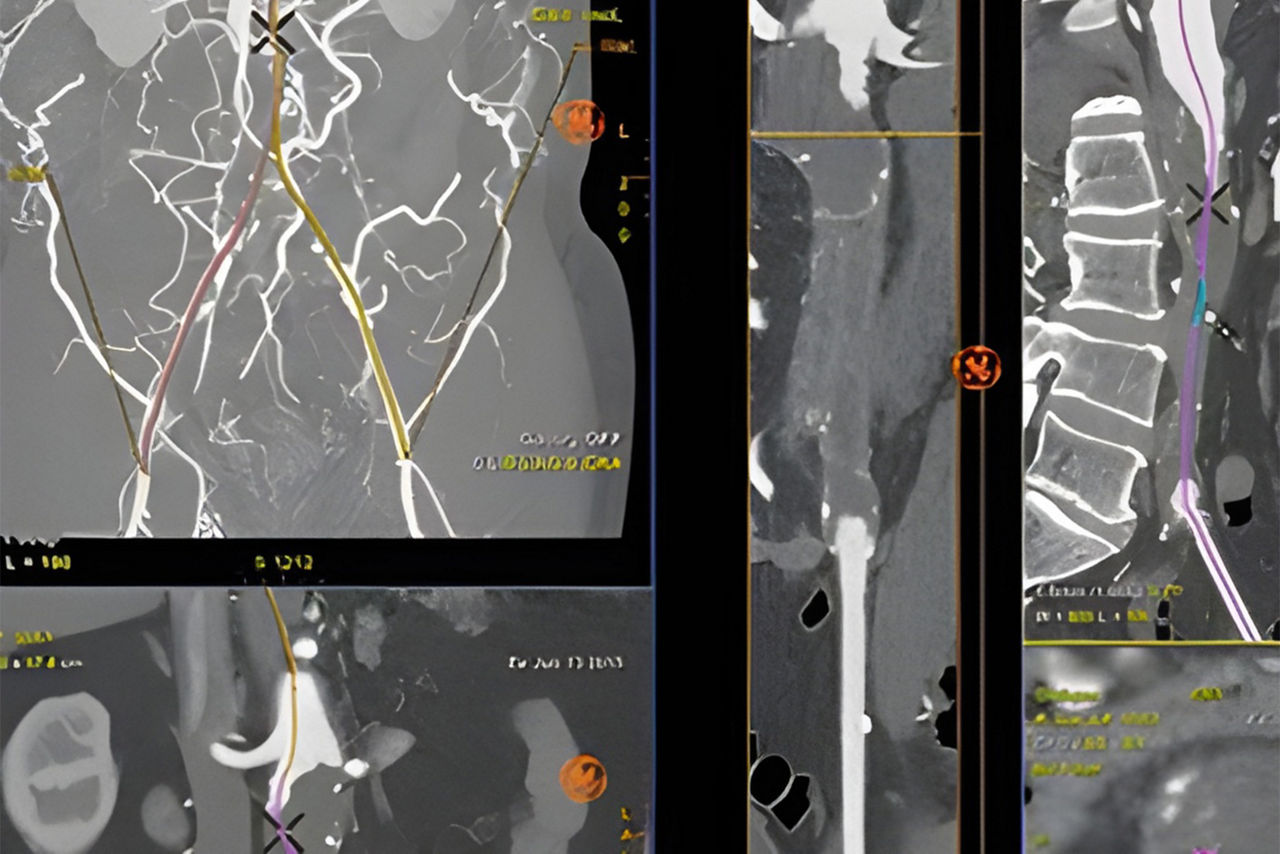

Vessel assist for peripheral

Vessel ASSIST delivers accurate and easy anatomy segmentation and accurate vessel quantification from 3D volumes. It also offers advanced 3D roadmap and augmented image guidance capabilities to guide catheter with confidence.

Plan

Automatically extract the bone and vessel anatomies. Edit vessel centerlines and bridge them through occlusions.

Select from the sub-volumes of vessels, centerlines, calcifications and landmarks to overlay on live fluoroscopy for 3D fusion guidance, with digital zoom, to guide recanalization.